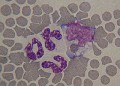

monocyte folié

Le noyau des monocytes est très polymorphe. Ici on parle de noyau folié. Chien.